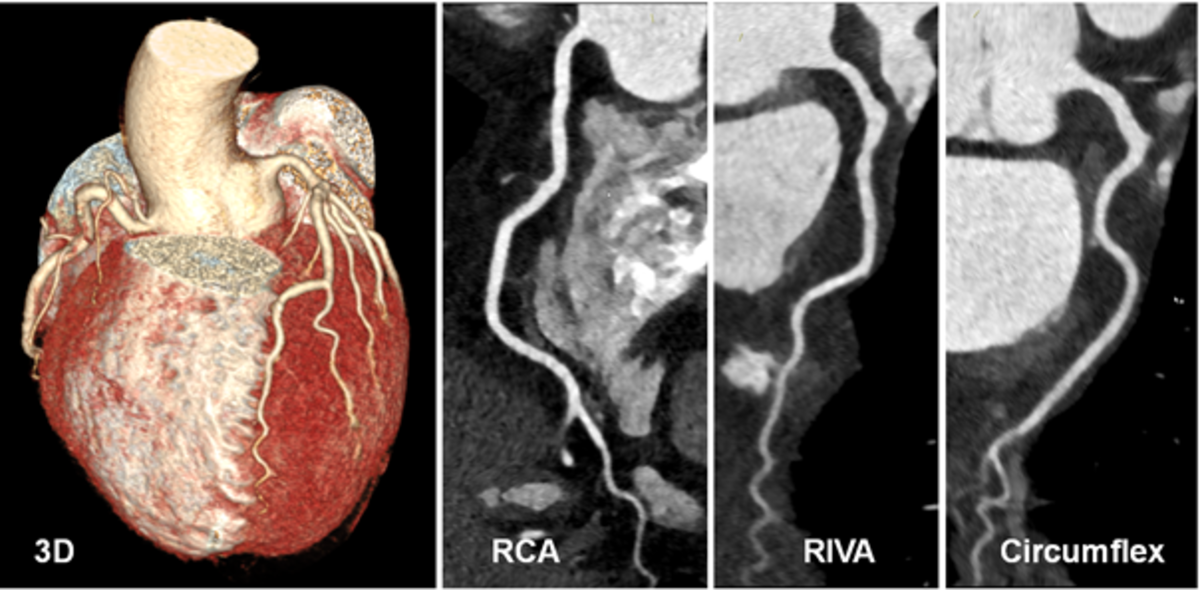

1) Ausschluss von Engstellen der Koronararterien:

Ein 55-jähriger Patient ohne kardiovaskuläre Risikofaktoren leidet seit einiger Zeit unter einem Engegefühl in der Brust bei körperlicher Belastung. In der CT-Koronarangiographie können wir Engstellen der Koronararterien und somit eine koronare Herzerkrankung sicher ausschließen. Für diese Information war vor wenigen Jahren noch eine Herzkatheteruntersuchung erforderlich. Diese war durch die Information der CT-Untersuchung nicht mehr erforderlich.